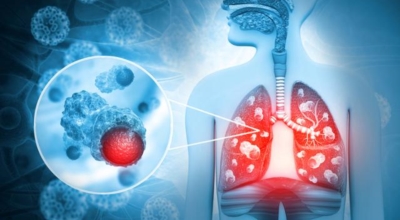

6. 폐암 초기증상 - 혈담

두번째 폐암 초기증상으로 혈담이 있는데 혈담은 쉽게 말해 가래에 피가 섞여나오는 경우입니다. 폐암이 폐 중앙부 기관지 부분과 근접해 있으면 나타나게 되는 혈담은 폐암환자의 25%이상이 경험하는 증상이므로 만에 하나라도 기침을 할 때 심한가래나 혈담이 섞여 나온다면 즉시 병원에 방문하시기 바래요.